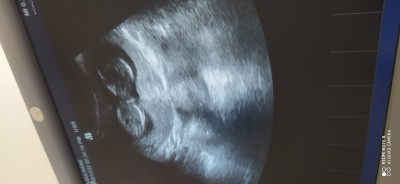

cinsiyet tahmini resimli sizce

14 haftalgiz sizce nedir

Kız bebiş canm

Erkek olunca çıkıntı yukarıda oluyor bide erkeklerin kemik yapısı daha farklı canm doktorunuz tahminde bulunmadı mı hiç haftana göre belli olurdu

Bulundu emin olmadi 17 de kesin dicem dedi kızların kemik yapısı nasilki

Senin attığın ultrason resmi gibi kızların kemik yapısı :) doktorunuz ne dedi

Kiz tahmin etti ama nasıl tatlı bisey bu